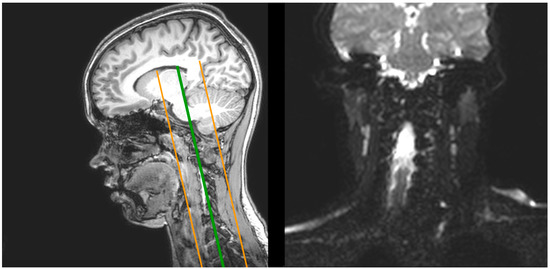

2.1. Magnetic Resonance Imaging (MRI)

| T1 | dMRI | |

| Sequence type | Turbo field echo | Diffusion-weighted single shot spin echo |

| Repetition time | 8.1 ms | 9000 ms |

| Echo time | 3.7 ms | 86 ms |

| Flip angle | 8° | 90° |

| Echo train length | 170 | 59 |

| No. of slices | 240 | 140 |

| B-value | - | 1000 s/mm2 |

| No. of gradient directions | - | 61 |

| Orientation | Sagittal | Axial |

| Acquisition duration | 359 s | 696 s |